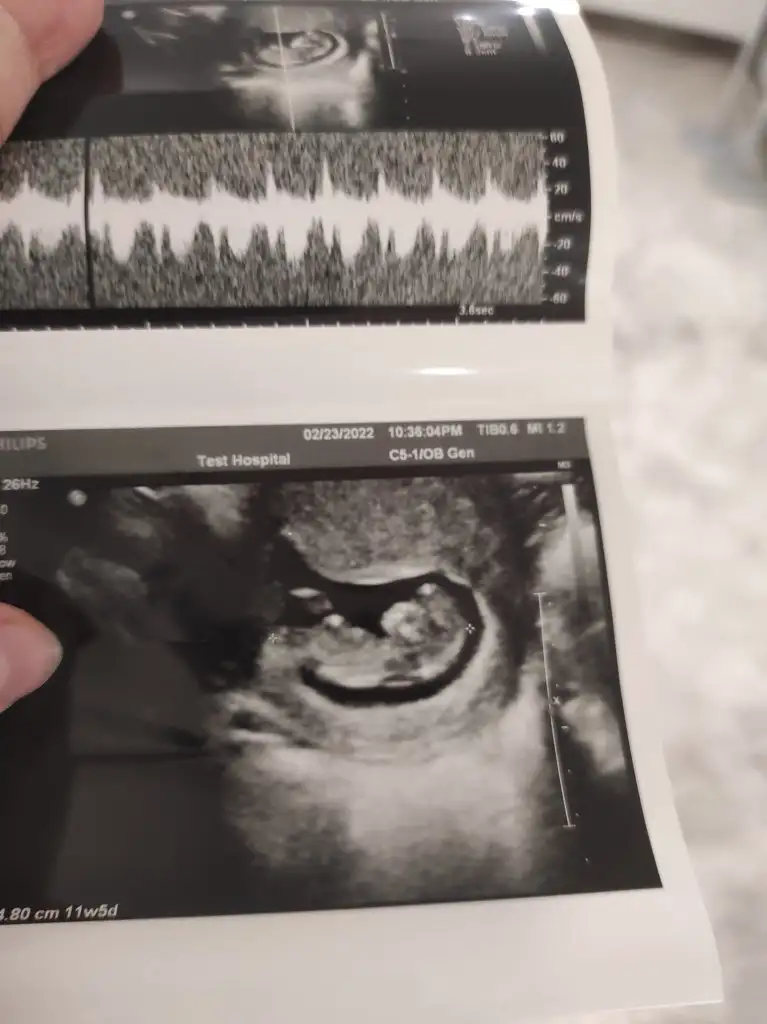

bi baksana kuzucum sana zahmet, benim 10+3 te 185 çıkmış kalp atışı. 11. Haftadan sonra yavaşlıyormuş 120-160 arasına geliyormuş.

Eve gidince atıcam sana var ama ayrıntılı cekmemişim görünmüyor galiba canım bu 11+5

Kalp atışı nasıl yazıyor diye soranlar olmuş benim alttaki şekilde gözüküyordu

Eklentiler

• 733C9492-0297-44BA-8763-C48654CB50AF.webp

733C9492-0297-44BA-8763-C48654CB50AF.webp

41 KB · Görüntüleme: 98